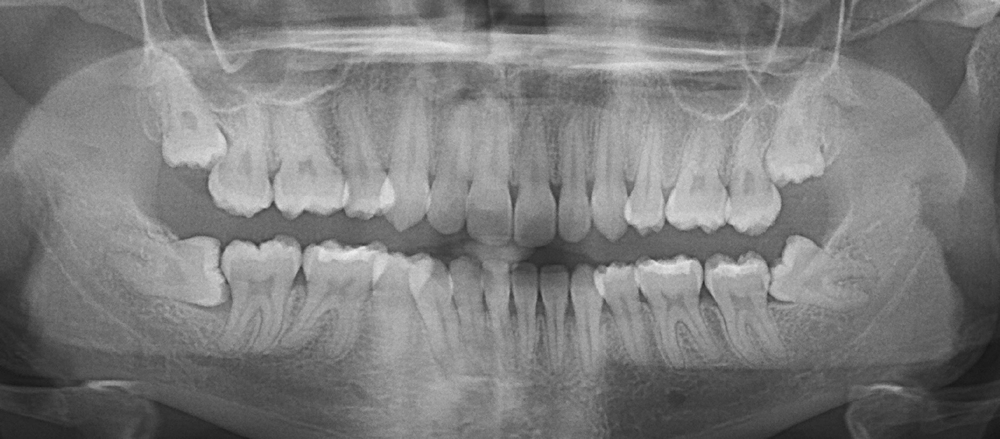

Но всё ли так просто? Надо ли удалять их всем подряд? Или, наоборот, стоит бороться за каждый «родной» зуб до последнего? Разбираемся, когда зубы мудрости действительно стоит удалить, а также какие последствия ждут, если игнорировать проблему. Это третьи моляры, которые прорезаются последними — обычно в возрасте от 17 до 25 лет. Но часто бывает так, что: Если зуб не выходит полностью, он может «застрять» в кости и вызывать хроническое воспаление — ретенцию. Такие зубы не участвуют в жевании, но создают гнойные очаги под десной. Когда зуб прорезается частично, над ним образуется «капюшон» из десны. Под него попадает еда, бактерии, и начинается воспаление: боль, отёк, температура. Восьмёрки могут давить на седьмые зубы, разрушая корни и вызывая кариес в труднодоступных местах. Если планируется исправление прикуса, удаление восьмёрок часто необходимо, чтобы дать место для перем

Это третьи моляры, которые прорезаются последними — обычно в возрасте от 17 до 25 лет.

• для них нет места в челюсти,

• они растут под углом,

• не прорезаются полностью (или вообще остаются в кости),

• и даже давят на соседние зубы, вызывая боль, воспаление и смещение прикуса.

Ретинированный (не прорезавшийся) зуб

Если зуб не выходит полностью, он может «застрять» в кости и вызывать хроническое воспаление — ретенцию. Такие зубы не участвуют в жевании, но создают гнойные очаги под десной.

Перикоронит — воспаление капюшона

Когда зуб прорезается частично, над ним образуется «капюшон» из десны. Под него попадает еда, бактерии, и начинается воспаление: боль, отёк, температура.

Нагрузка на соседние зубы

Восьмёрки могут давить на седьмые зубы, разрушая корни и вызывая кариес в труднодоступных местах.

Киста или резорбция

Иногда рядом с непрорезавшимися зубами формируются кисты или киста-фолликулы, которые могут разрушать кость челюсти.